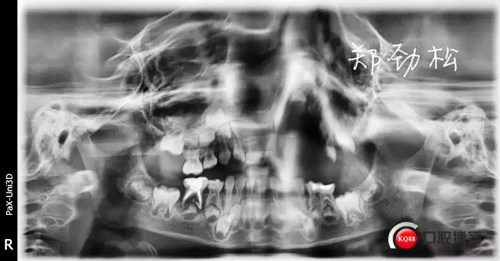

412058.jpg

一月后永久充填復(fù)查時(shí)可見(jiàn)炎癥明顯好轉(zhuǎn),近中根超充的糊劑也吸收了,臨床癥狀也消失了。